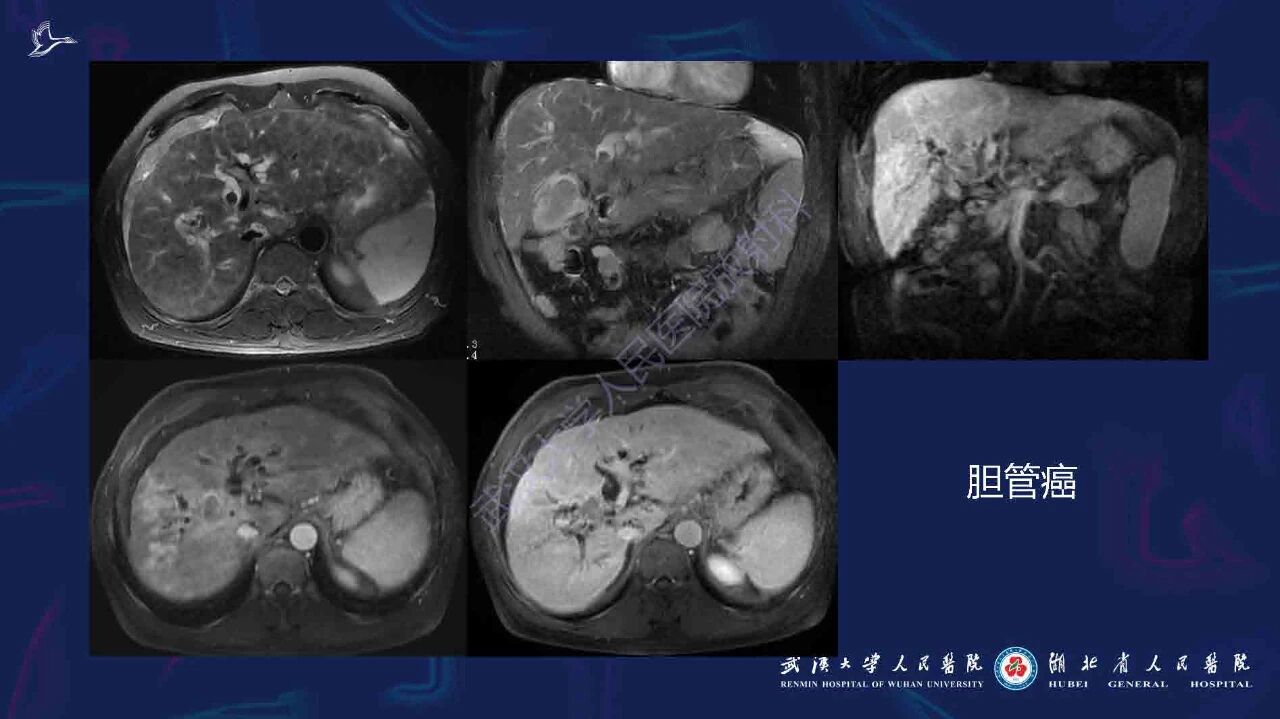

肝硬化伴肝内局灶性病变影像诊断